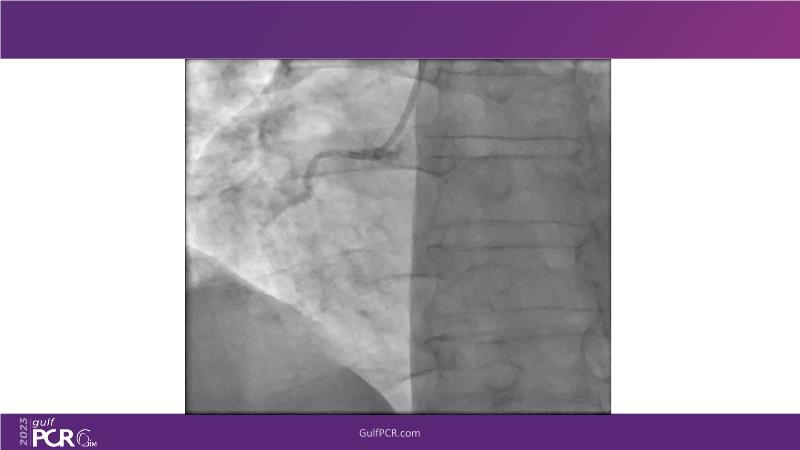

This session is a valuable resource for grasping innovative strategies in handling bifurcation and extended diffuse lesions through dedicated stenting solutions. Explore insights into the advanced Myval next-generation THV technology, unveiling its distinctive features, procedural advantages, and clinical outcomes across a diverse patient pool. Gain understanding into the CorAlign technique, ensuring accurate commissural and coronary alignment while maintaining coronary access. Additionally, delve into the techniques for precise sizing, positioning, and deploying of Myval THV.

- To understand novel tools and techniques for effective management of bifurcation lesions and long diffused lesions using dedicated stenting solutions